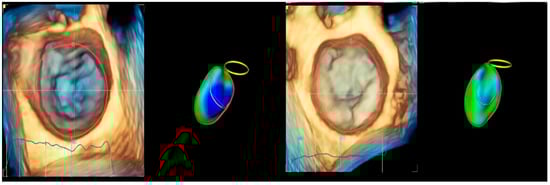

In healthy humans, the MA is essential for the structural and functional integrity of the MV complex, reducing stress exerted by LV forces on the mitral valve leaflets [32,37]. During the LV contraction, the MA folds from early to mid-systole and increases its saddle-shape configuration. During late systole to diastole, the MA gradually expands back [38]. Four-dimensional echocardiography has significantly enhanced the understanding of the anatomy of the mitral valve apparatus [39,40,41]. RT4DE is a useful imaging technique for identifying differences in MA shape and function in cardiac diseases [8]. MA morphological parameters provided by RT4DE are AA, AP, APd, PM-ALd, CD, ITD, AH, NPA, and MAA [38,42] (Figure 5).

Annular characteristics are abnormal in patients with DCM and FMR. Chronic LV remodeling produces enlarged, flat, and adynamic [43,44,45] MA, with apical displacement of papillary muscles (PMs) [46] (Figure 9). The MA contraction at early systole is decreased or absent [45,47,48,49,50,51]. Studies have shown that the attenuated contractility of MA in FMR is significantly associated with a loss of physiological morphology [52,53,54,55,56]. MA dilation in DCM does not comprise the entire annular circumference. The most damaged is the posterior segment. The dilation is asymmetric, increasing septal–lateral diameter, impeding the leaflet’s coaptation, and resulting in FMR [34].

Figure 9.

Mitral annulus shape: (left) normal subject—saddle shape of mitral annulus; (right) patient with chronic left ventricle remodeling—enlarged, flat, and adynamic mitral annulus.

The anatomical features of the MVA in patients with DCM and FMR can be described as follows: increased distance between the MA and interregional zone, increased annular nonplanarity scalar angle, and increased anteroposterior and posteromedial–anterolateral diameters, with loss of the typical saddle shape of the MA [49,50,51]. The evaluation of MA geometry and function, as well as the determinants of MA remodeling, is essential for understanding the pathophysiology and severity of FMR in patients with DCM, particularly in the context of reparative surgery [57,58].